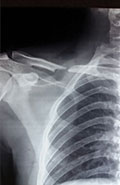

Case 5: Clavicle fracture

X-RAY 1

Displaced fracture right clavicle

Post operative x-ray